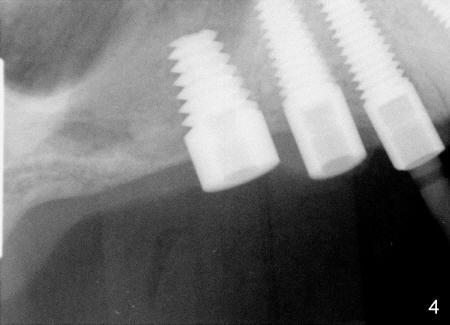

In fact, healing screws had been removed (Fig.1). There is space inside the well of the implant #5 and less obvious in that of #3 (because its wall is thicker). When implants tilt, the opening of the wells is visible (Fig.2-4).

A post guide (Fig.2: P) was inserted to the well of #5 implant as a guide for #4 pilot drill and continually for a drill with larger diameter (Fig. 3 D). Implant placement was a breeze (Fig.4). Two months later, three of the straight abutments (0 degree) were also parallel to each other.